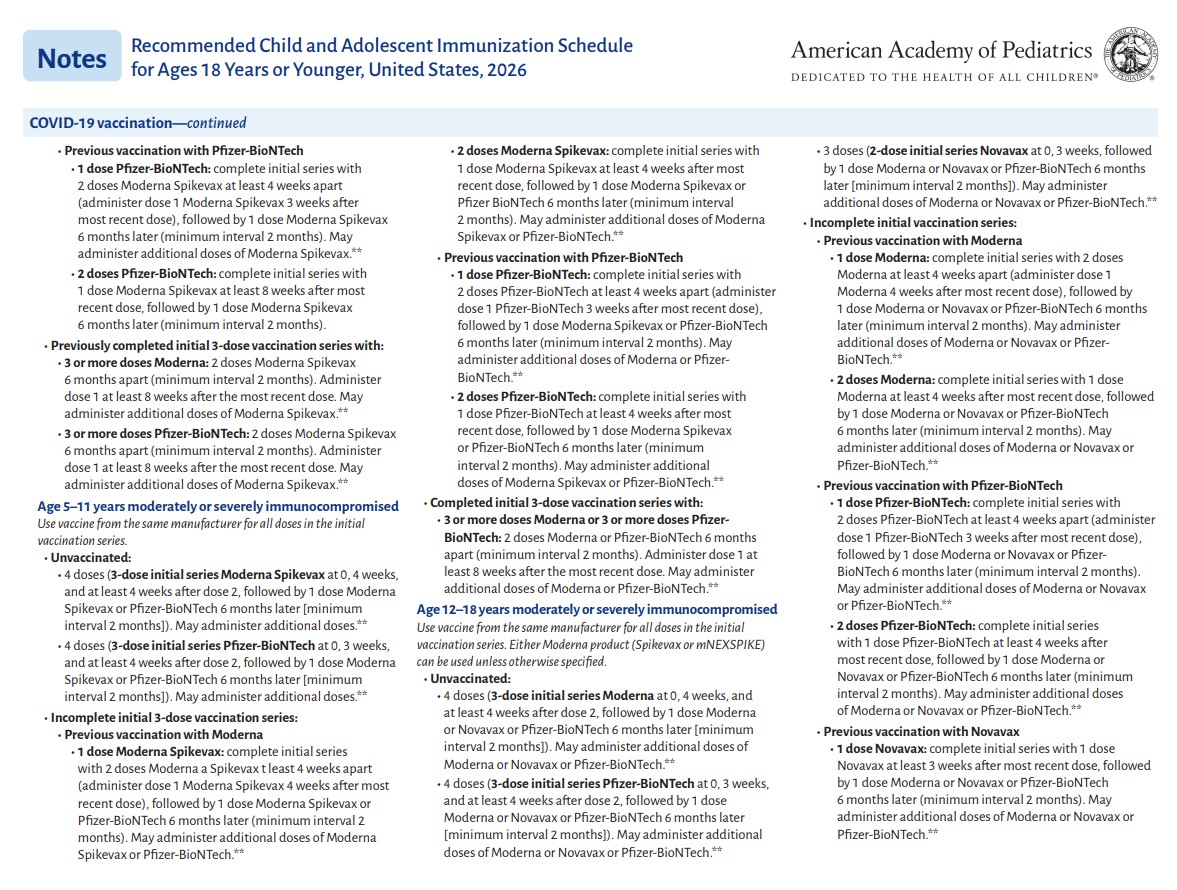

p 2